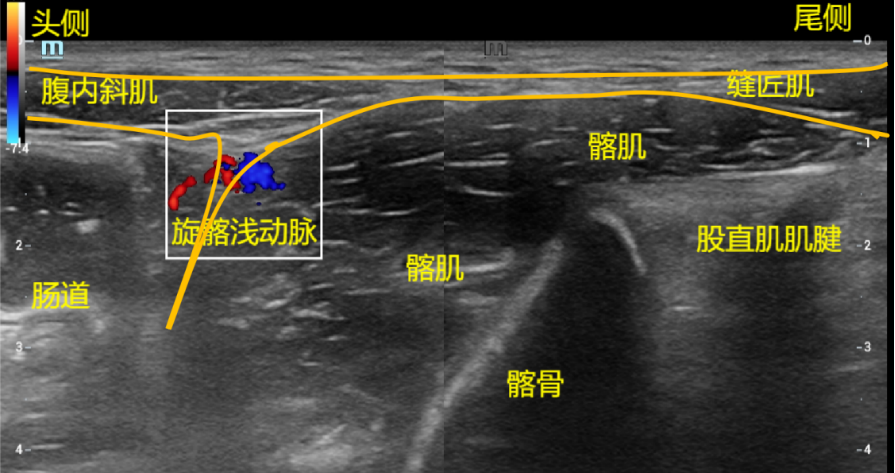

扫查方法:关键点是先找髂肌,再顺髂肌找其他,因为髂肌的上方就是髂筋膜。探头垂直放置在髂前上棘与耻骨联合连线外1/3处,也即是垂直放于腹股沟韧带处,探头中点位于腹股沟韧带上方。上下滑动找髂前下棘和髂骨,与髂骨相贴的就是髂肌,髂肌表面上高亮回声的就是髂筋膜,药物注射在髂肌与髂筋膜之间的高亮回声间隙中。该部位其他结构是:探头人体的尾侧是缝匠肌、探头人体的头侧是腹横肌或腹内斜肌。

穿刺方法:平面内法,从人体尾侧进针,即髂前上棘内下方缝匠肌处,药物注射在腹内斜肌或腹横肌与髂肌之间的髂筋膜间隙内。观察局麻药液在髂筋膜与髂肌之间的间隙内扩散。